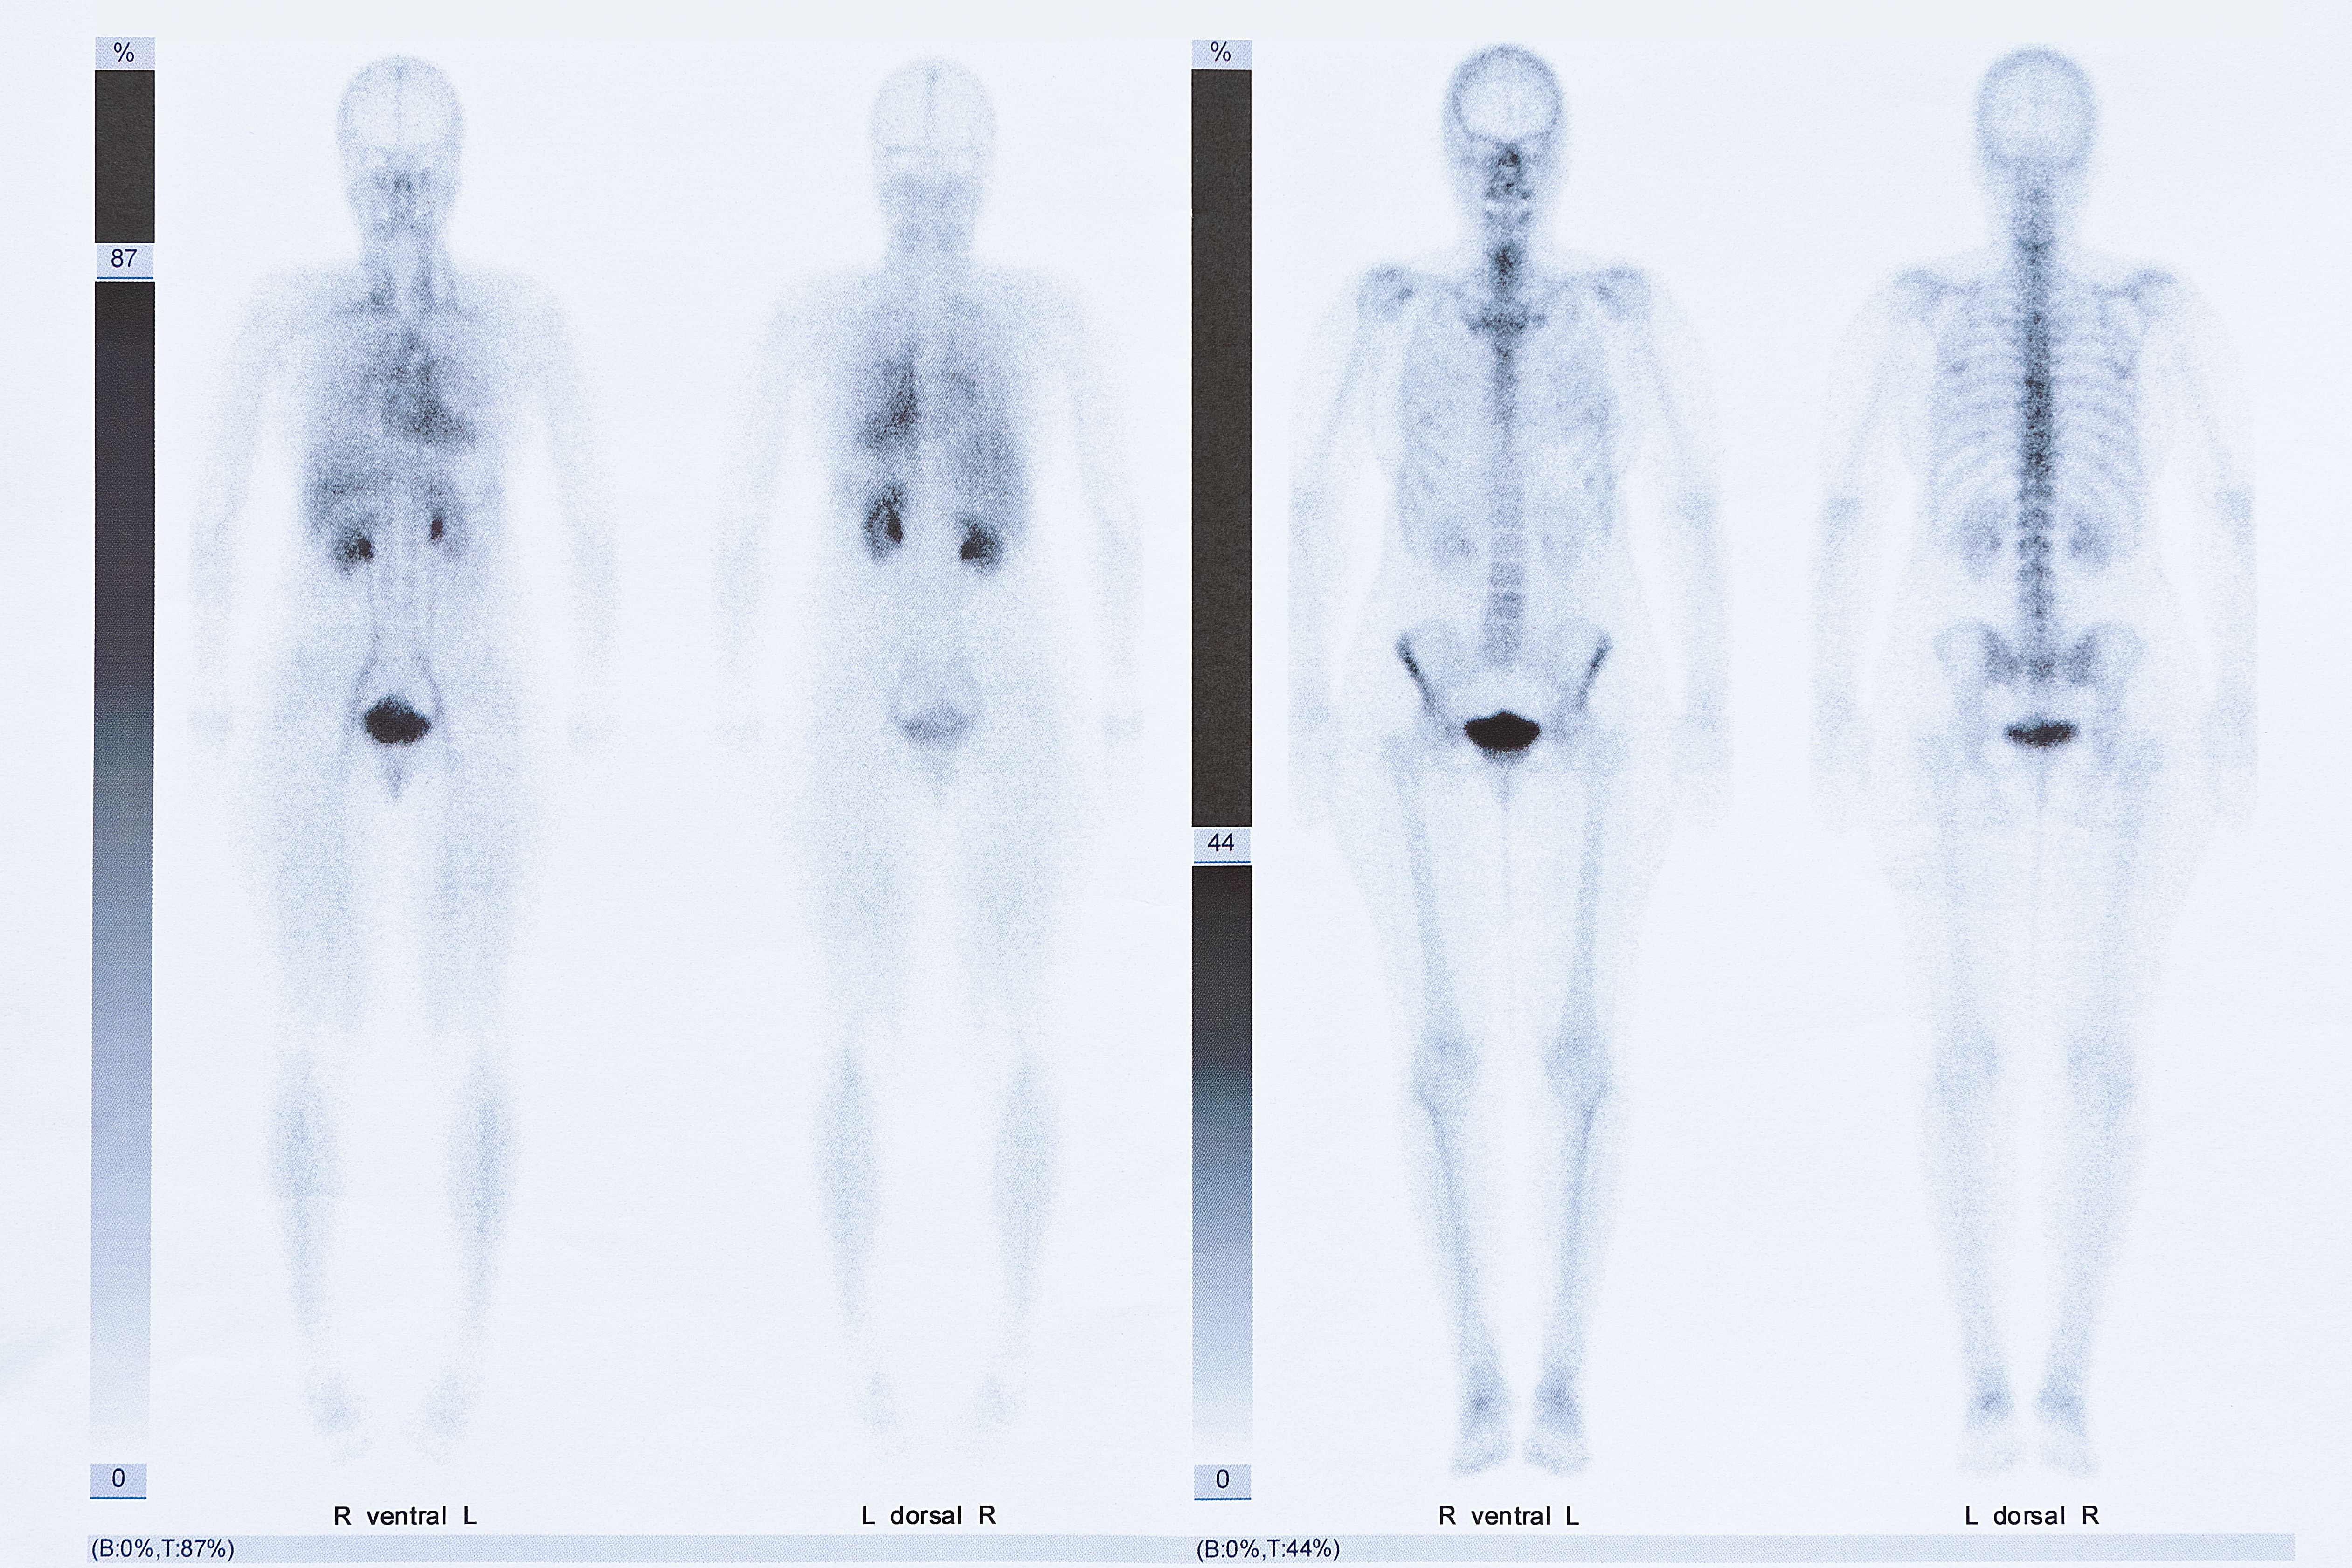

Symbolic image: Example of a scintigraphy

The generation of synthetic datasets using generative AI offers a promising solution to these challenges. By synthesizing medical imaging data, AI systems can be trained on a broader range of disease patterns without relying on rare or difficult-to-access patient data. This approach was pursued by a research team from the Division of Nuclear Medicine (Department of Biomedical Imaging and Image-guided Therapy) at MedUni Vienna, in a recently published study. A generative AI was trained on more than 9,000 scans from routine clinical examinations in the scintigraphy outpatient department. The model was then used to generate a synthetic image dataset that replicates the characteristic features of real medical imaging data but is entirely newly generated, ensuring that no patient-related information can be traced.

The quality of the synthetic data was evaluated by four independent physicians. They found no discernible difference between the synthetically generated and real imaging data. The relevance of the synthetic data was further confirmed by an independent research group at the University of Brescia. There, a team of researchers developed an AI system to detect patients suspected of having cardiac amyloidosis or bone metastases, trained using the synthetic imaging data generated in Vienna. The system was subsequently validated using data from more than 6,000 patients from four independent institutions in Europe and Asia. The results showed that integrating synthetic data significantly improved the diagnostic accuracy of the AI system.